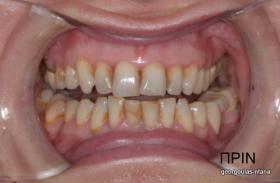

Η ασθενής ήταν δυσαρεστημένη με την αισθητική εμφάνιση των δοντιών της, κυρίως των άνω και κάτω πρόσθιων, τα οποία είχαν εκτεταμένες εμφράξεις σύνθετης ρητίνης που είχαν αποχρωματιστεί. Κάποια από τα οπίσθια δόντια έφεραν κακότεχνες προσθετικές αποκαταστάσεις (γέφυρα, στεφάνες) ενώ κάποια άλλα ήταν τερηδονισμένα. Η ασθενής επιθυμούσε το καλύτερο δυνατό αισθητικό αποτέλεσμα. Για το λόγο αυτό αποφασίστηκε να τοποθετηθούν μεμονωμένες ολοκεραμικές στεφάνες από διπυριτικό λίθιο (Emax) σε όλα τα δόντια της άνω και κάτω γνάθου, ώστε να εξασφαλιστεί το καλύτερο αισθητικό αποτέλεσμα. Χρησιμοποιήθηκε η τεχνική MIPP (Minimally Invasive Prosthetic Procedures) με ελάχιστη αποκοπή οδοντικών ιστών και μονολιθικές αποκαταστάσεις Emax στα οπίσθια δόντια.  Στη θέση του κάτω αριστερού πρώτου γομφίου, ο οποίος έλειπε και είχε αντικατασταθεί με γέφυρα που στηρίζονταν στα διπλανά δόντια, αποφασίστηκε να τοποθετηθεί εμφύτευμα. Σε όλη τη διάρκεια της θεραπείας η ασθενής ήταν καλυμμένη με προσωρινές προσθετικές αποκαταστάσεις.